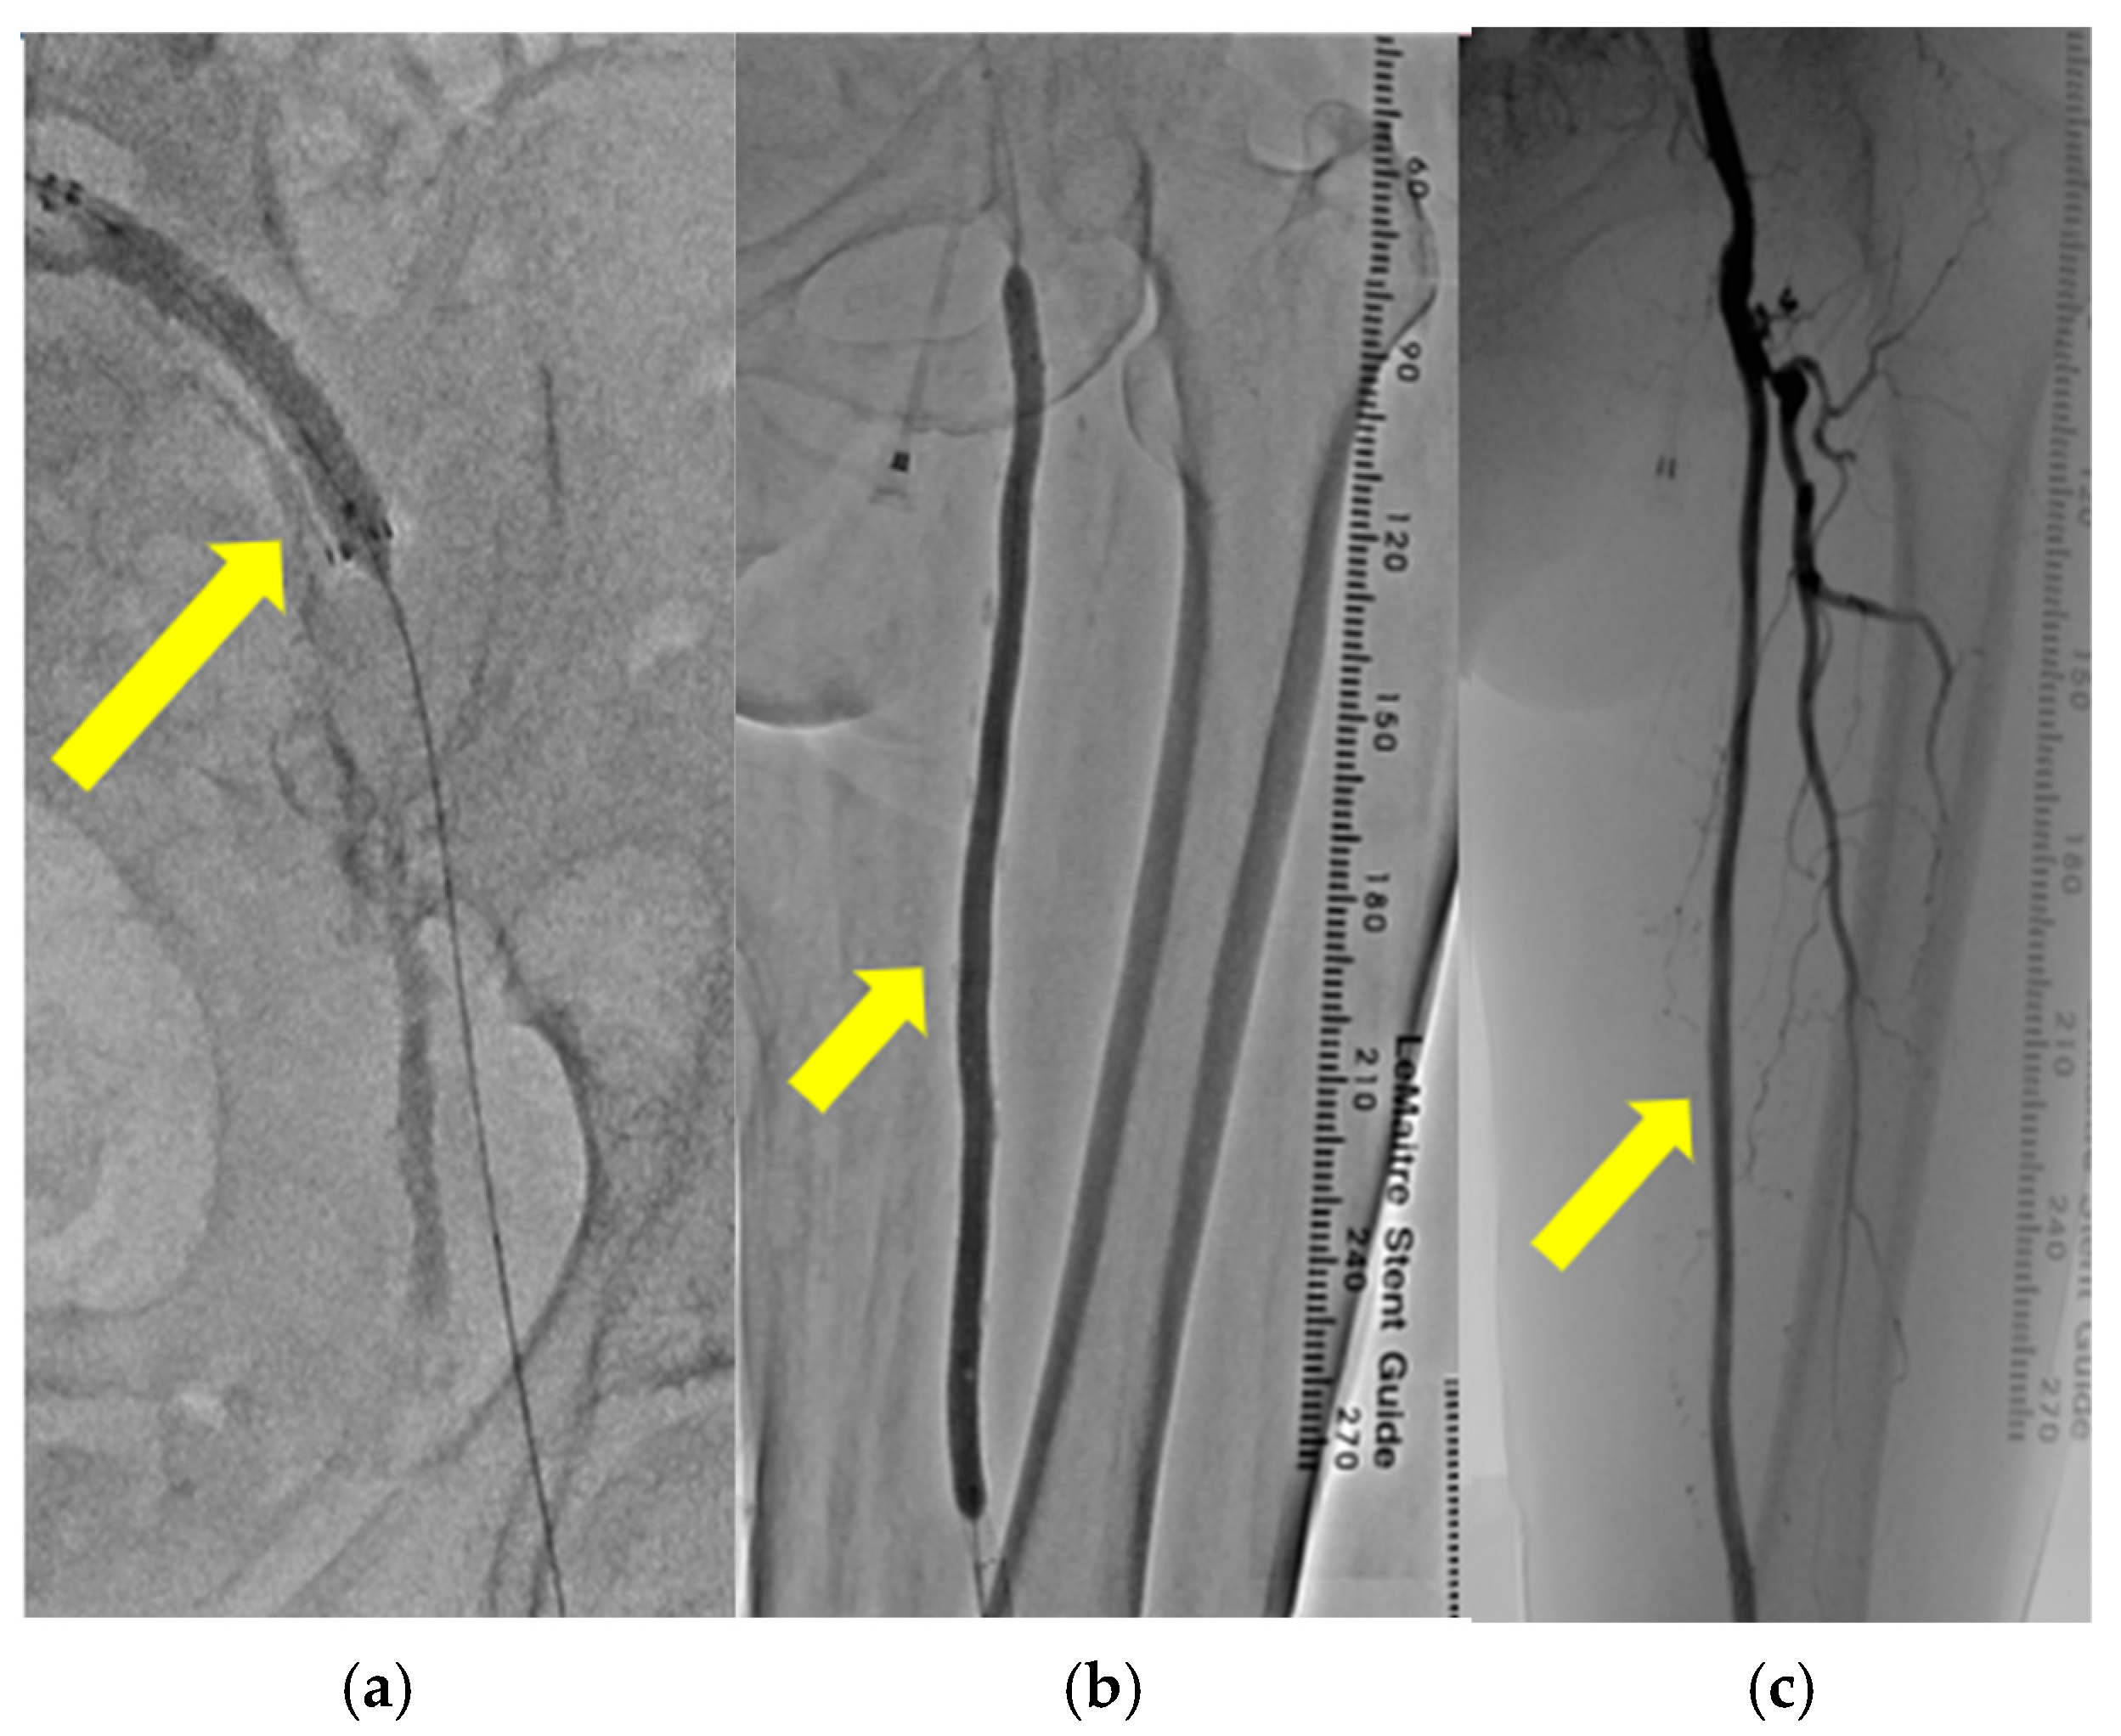

To restore the blood flow in the lower leg, left CIA stenting (Figure 5a) and SFA balloon angioplasty (Figure 5b) were performed. The blood flow in left SFA dramatically improved through these catheter surgeries (Figure 5c).

Figure 5.

(a–c): Catheter angiography revealed the insertion of a stent into the left common iliac artery (yellow arrow) (a). Catheter angiography revealed balloon angioplasty performed on the left superficial femoral artery (yellow arrow) (b). Catheter angiography revealed enhanced blood flow in the left superficial femoral artery after endovascular therapy (yellow arrow) (c).